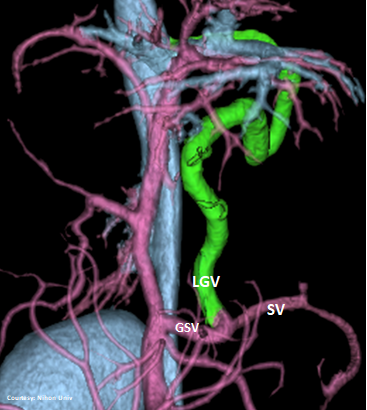

PRE-HEPATIC ENTRANCE

(GSV present)

“LGC +RGV +SGV”

Left Gastro-Caval Shunt with Right Gastric Vein and Short Gastric Vein contributions

Courtesy: Nihon Univ

WEISSE 2022